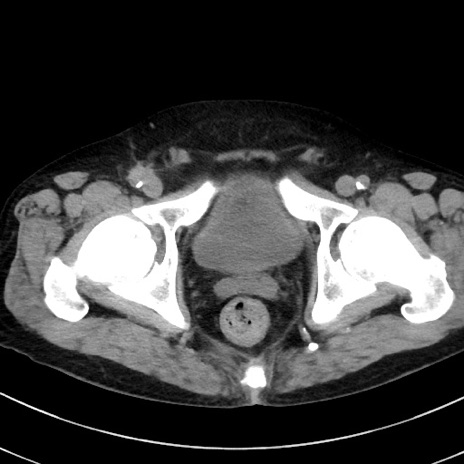

症例38(横断像)

【症例】70歳代 男性

【主訴】腹痛・嘔吐

【現病歴】昨晩より、嘔吐・腹痛あり。今朝になっても嘔吐あり。来院。

【既往歴】心臓バイパス手術、開腹胆摘、腸閉塞

【身体所見】BP 107/71mmHg、HR 116/min、腹部:平坦、軟、下腹部に軽度圧痛あり。反跳痛なし。

【データ】WBC 15100、CRP 0.32